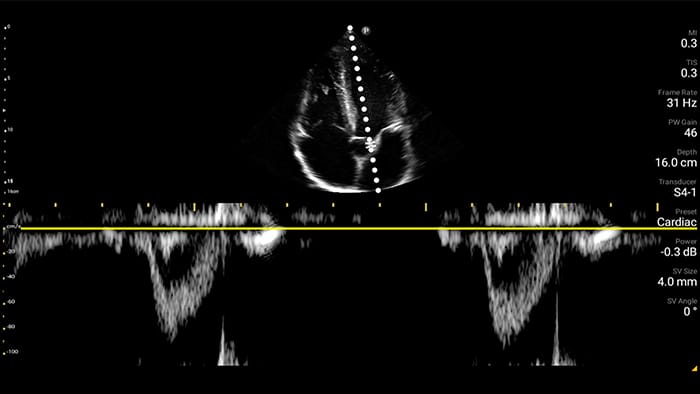

Act faster to protect their heart

When seconds count, portable ultrasound can make the difference. Lumify can provide the high-definition imagery you need whenever and wherever you need it.

Lumify S4-1 broadband phased array transducer